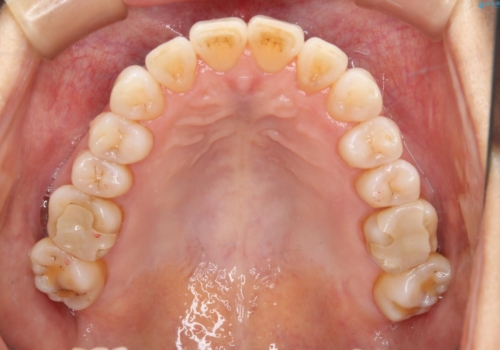

前歯の反対咬合、奥に引っ込んでしまっている歯をインビザラインで治療する

上の前歯の反対咬合があり、治療の途中で下の前歯を乗り越える必要があります。